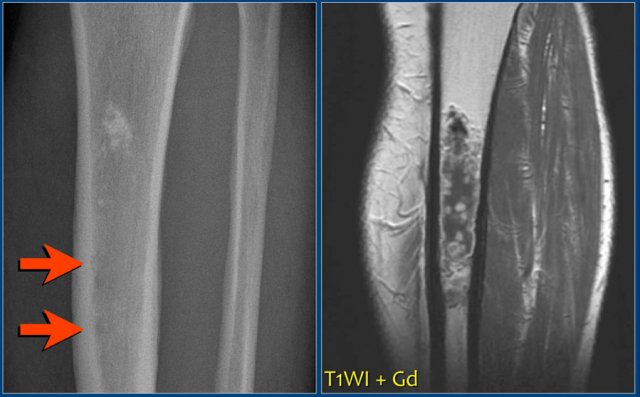

On the left a chondrosarcoma in the proximal tibia diaphysis.

The tumor is recognized by subtle calcifications in the proximal part.

The distal border is not well defined.

Notice endosteal scalloping at the medial side which is a hallmark of chondrosarcoma.

MR better defines the extension of the lesion.

MRI also demonstrates the endosteal scalloping.